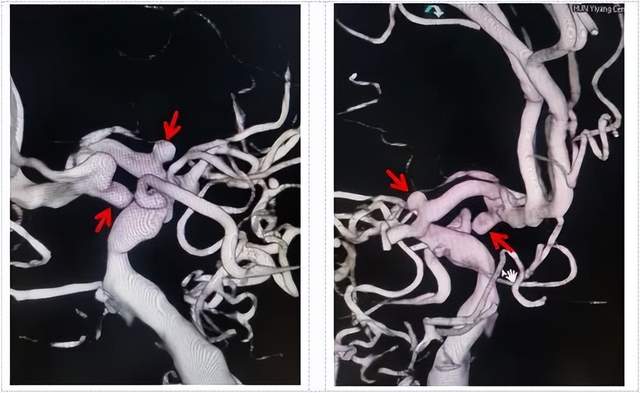

术前DSA检查颅内多发动脉瘤

面对该患者前交通动脉和右侧大脑前动脉多发动脉瘤合并烟雾病,无论是开颅动脉瘤夹闭还是血管内介入栓塞治疗难度都比较大。